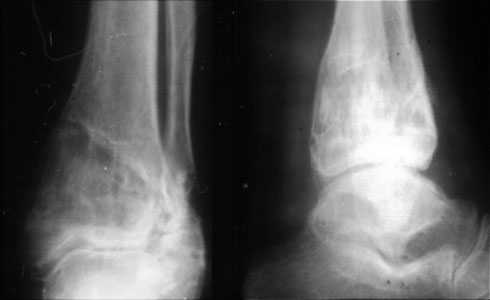

Скорее это перелом пилона 43В

Согласен, тут деформация меньше, но все-таки заметная, почти 20 градусов. Я бы устранял ее как на приложенной картинке.

При таком варианте с аппаратом все легко и просто. С пластиной - должны быть трудности. Может быть, следовало бы планировать коррекцию как-то иначе? Как?